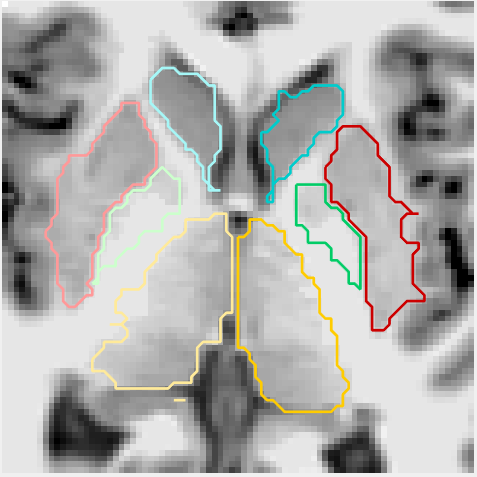

Figures 6 and 3.2 give visual examples of segmentations obtained by our 3D FCNN architecture and standard references contoured by FreeSurfer.

It can be observed that the segmentations generated by our proposed architecture are significantly smoother than those of FreeSurfer, regardless of the subject group (i.e diagnosis, age, site employed or not in training). We also notice that our system is better at identifying thin regions in the structures of interest, for instance, the lower extremities of pallidum (green regions).

Site NOT used in training

Figure 7: Visual examples of our 3D FCNN architecture compared with the references standard contoured by FreeSurfer for three test subjects from sites not used in training.